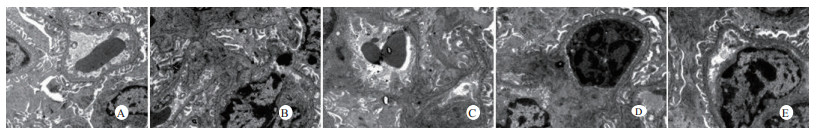

光镜下可见,假手术组肺泡大小形态均匀,结构清晰,肺泡腔内无出血和白细胞浸润;感染性休克组肺泡壁破坏严重,血管壁和肺泡间隔明显增厚;U50488H+感染性休克组大部分肺泡腔均匀一致,肺间隔略增厚,肺泡壁轻度水肿,但出血和白细胞浸润情况比感染性休克组明显减轻(图 1)。假手术组心肌细胞大小一致,排列整齐,核浆比正常,心肌细胞核呈椭圆型,胞浆均匀红染;感染性休克组心肌细胞肿胀,体积明显增大,细胞核大而异型,核内染色质固缩、边集,白细胞浸润明显增加;U50488H+感染性休克组多数心肌细胞形态相对正常,少数心肌细胞呈现脂肪变性(图 2)。假手术组肝细胞结构完整,肝小叶形态正常;感染性休克组肝细胞显著肿胀、呈空泡样和点状/小片状坏死;U50488H+感染性休克组肝细胞轻度肿胀,未见明显坏死灶、肝血窦扩张和炎性细胞浸润(图 3)。假手术组肾组织结构大致正常;感染性休克组肾小管细胞轻度水肿、空泡变性;U50488H+感染性休克组肾小管形态大致正常,间质无明显出血水肿(图 4)。

| A:假手术组,B:感染性休克组,C:U50488H+感染性休克组,D:nor-BNI+U50488H+感染性休克组,E:nor-BNI+感染性休克组 图 3 各组光镜下肝组织病理学改变(HE×400) Fig 3 Histopathological features of liver(HE×400) |

扫描电镜下可见,假手术组肺泡形态完整,肺泡壁光滑;感染性休克组肺泡明显压缩畸形,肺泡隔肿胀、扭曲、隆起;U50488H+感染性休克组肺泡形态大致完整,少数肺泡壁肿胀受损(图 5)。透射电镜下可见,假手术组心肌细胞形态正常;感染性休克组心肌细胞溶解、坏死、肌纤维断裂;U50488H+感染性休克组心肌细胞大致正常,无明显坏死(图 6)。假手术组肝细胞形态正常,毛细胆管未见扩张;感染性休克组肝细胞大片坏死,毛细胆管明显扩张;U50488H+感染性休克组肝细胞形态大致正常,毛细胆管略扩张(图 7)。假手术组肾小管上皮细胞形态狭长,核卵圆形,位于基底部;感染性休克组肾小管上皮断裂,微绒毛缺失;U50488H+感染性休克组肾小管上皮细胞大致正常,微绒毛不平滑,但无明显坏死(图 8)。

| A:假手术组,B:感染性休克组,C:U50488H+感染性休克组,D:nor-BNI+U50488H+感染性休克组,E:nor-BNI+感染性休克组 图 7 肝细胞透射电镜检查(×10 000) Fig 7 Transmission electronic microscopic photos of liver(×10 000) |

本研究还进一步观察了感染性休克大鼠重要脏器的病理学变化与超微结构。结果发现,感染性休克时,肺泡壁破坏严重,血管壁和肺泡间隔明显增厚,炎症细胞浸润较多,肺泡明显压缩畸形,肺泡隔肿胀,扭曲,隆起。该结果与潘景业等的报道一致。同时实验发现,U50488H可减轻感染性休克肺泡壁出血水肿与肺组织炎性细胞浸润,抑制肺间隔增厚。实验还观察到感染性休克大鼠心肌纤维肿胀、扭曲、断裂、溶解,并由此导致心功能障碍。U50488H亦可减轻线粒体肿胀崩解和心肌细胞溶解与坏死,可能与U50488H减轻心肌抑制有关[12],具体机制与分子通路尚需进一步实验验证。本研究还观察到感染性休克大鼠肝细胞出现肿胀、空泡样脂肪变性和点状/小片状坏死,毛细胆管明显增多、扩张;肾小管细胞轻度水肿、空泡变性,肾小管上皮细胞微绒毛缺失,细胞崩解,肾小管上皮断裂。预先给予U50488H可显著减轻感染性休克肝细胞浊肿、肝血窦扩张和炎性细胞浸润;抑制肾小管上皮细胞核变形、微绒毛坏死和间质出血水肿。nor-BNI可阻断这一效应。上述结果均提示U50488H可通过激动κ-阿片受体,改善肝脏和肾脏血流量保护感染性休克肝脏和肾脏功能,具体机制可能和细胞凋亡等相关。